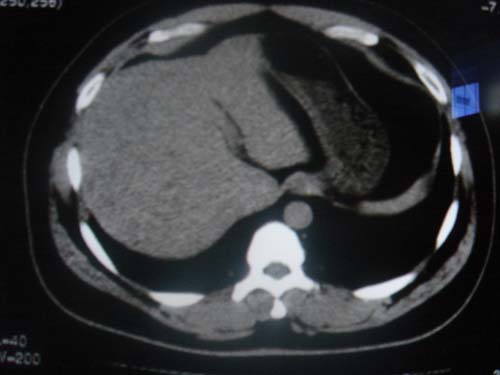

患者 男 40 右上腹不适 有胆囊息肉病史2年

最后二副图像示胆囊壁增厚,与肝分界欠清,建议强化ct或磁共振

平扫怀疑肝或胆囊病变,建议行增强吧!

片中示肝脏的ct值低于脾脏,肝脏右叶外缘部份凹凸不平,考虑脂肪肝,肝硬化可能。结合其检查如b超或ct增强检查。

肝右叶密度不均,脾大。强烈要求增强扫描除外浸润型肝癌。

建议薄层增强扫描